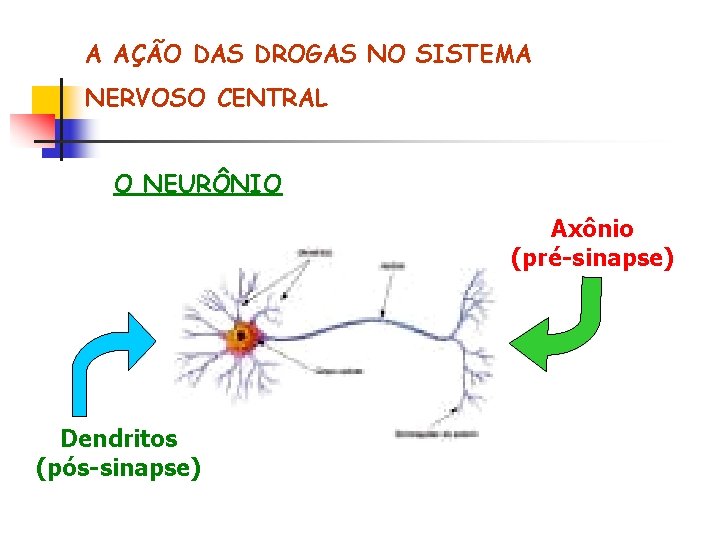

A AÇÃO DAS DROGAS NO SISTEMA NERVOSO CENTRAL O NEURÔNIO Axônio (pré-sinapse) Dendritos (pós-sinapse)